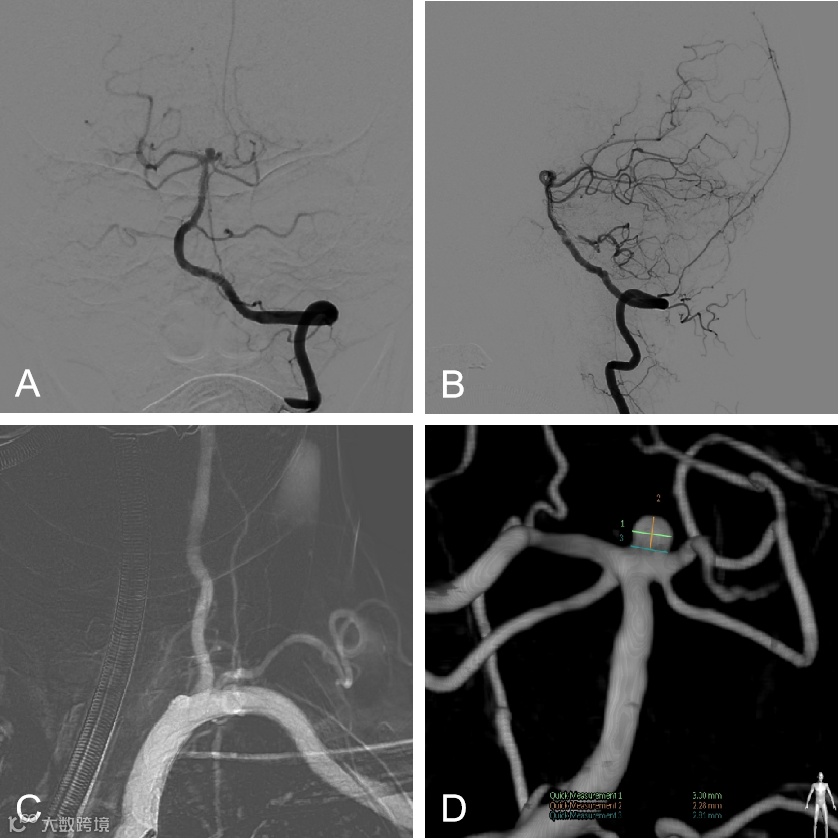

外院DSA示:基底动脉尖动脉瘤(图2 A,B)

图2

患者取仰卧位,全麻下右侧股动脉穿刺置入8F血管鞘,全身肝素化。5F单弯在泥鳅导丝引导下行全脑血管造影,可见基底动脉尖动脉瘤,左椎优势供血伴起始处迂曲,左侧非胚胎型大脑后动脉(图3,4)。

图3

图4